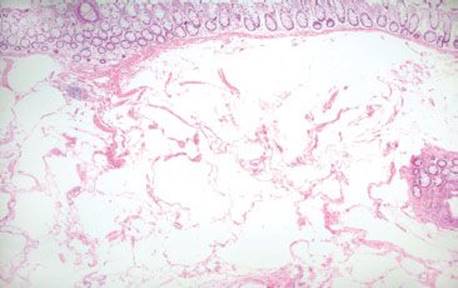

Figure 4.246 Air artifact. This resection case originated from a patient with bowel perforation. Note the large, billowing, cloudlike air pockets coursing through the submucosa. Although subtle cases of air artifact often raise the possibility of a lipoma, these particular air pockets are far too large, bizarre, and convoluted to be anything other than entrapped air.

Figure 4.247 Air artifact. Higher power shows the air pockets are pushing apart the normal cellular constituents (note the lymphoid aggregate in the upper left, vessels in the middle, and ganglion cells in the upper right). In addition, the air pockets have no endothelial lining (to suggest a lymphovascular space) or nuclei (to suggest an adipocyte), both helpful clues to the diagnosis of air artifact. Also, note there is no tissue response (there are no foreign body giant cells reacting to the displaced gas). This emergent bowel resection occurred almost immediately after the perforation, before the tissue had sufficient time to react to the infiltrating gas.

Figure 4.248 Air artifact. An alternative field shows large, bizarre air pockets (asterisks), which dissect the resident tissue. Lipomas do not tend to percolate around native structures such as ganglion cell clusters, nerves, fibrous tissue, and blood vessels, as seen in this example of an air artifact. Also, there is no epithelial lining and no nuclei to suggest a lymphovascular space or adipocytic lesion, respectively.